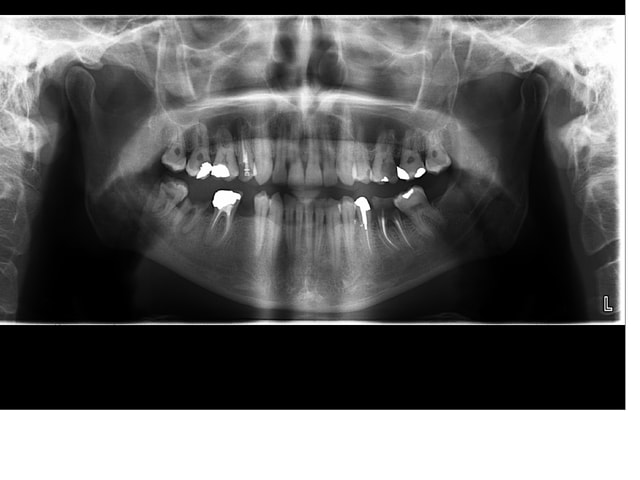

patient de ce soir.... j'hésite sur le système à utiliser pour le traitement de 14: protaper? reciproc? 100% manuel (probable).

En tout cas, je sens le petit défit!

oui oui le patient est au courant pour la chir à rétro ou l'implant

Mais ya quoi sur la 14 ajbsxf - Eugenol

14 nhl2ld - Eugenol